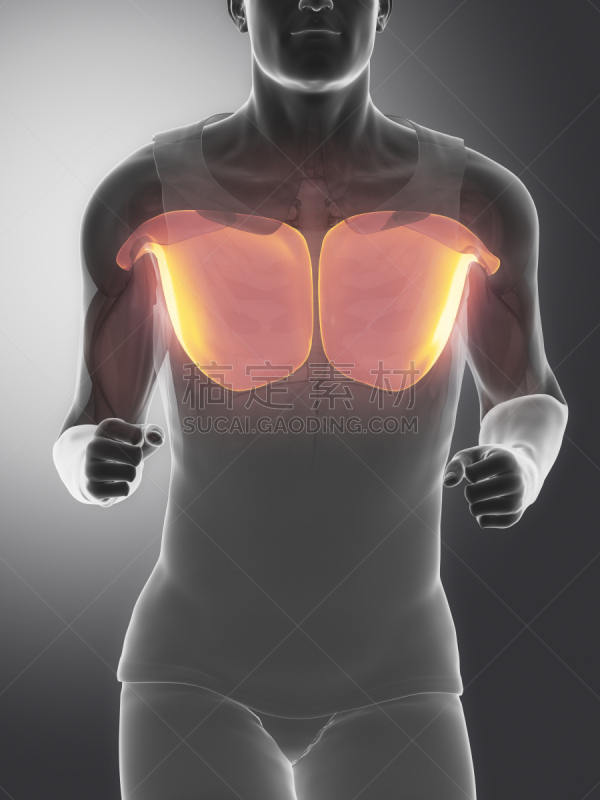

骨骼和肌腱解剖前视图详情

肌系统解剖学前视图详情

肌系统解剖学前视图详情

骨骼和肌腱解剖前视图详情